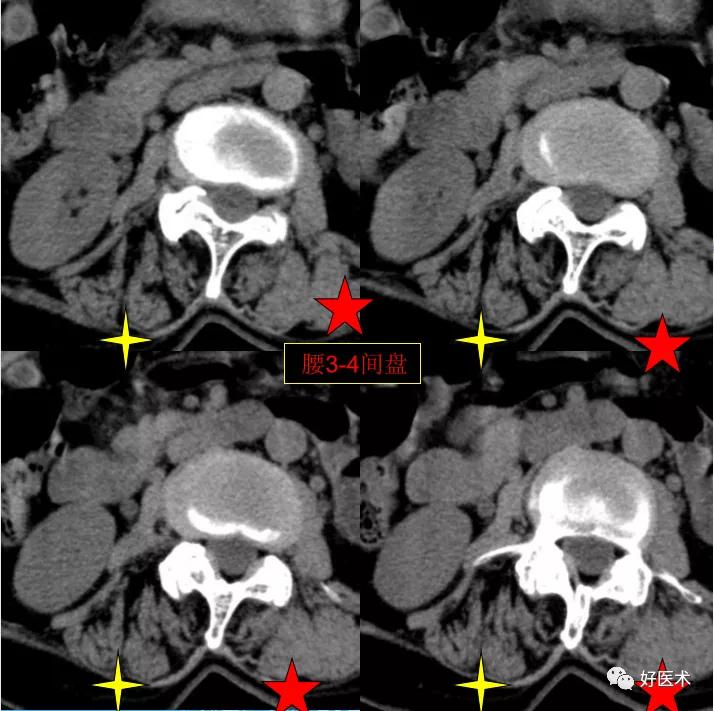

腰3-4间盘膨隆。

发现了什么?左侧竖脊肌较右侧明显肿胀饱满, 肌间脂肪间隙消失!!